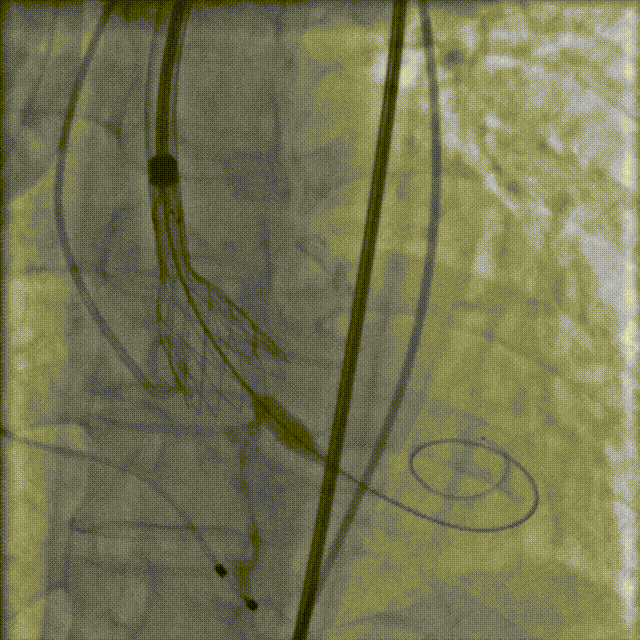

TaurusNXT植入过程

手术采用20mm Z-Med II球囊进行预扩张,植入AV23 TaurusNXT主动脉瓣。在左右重合位影像(cusp overlap view)下释放瓣膜达到工作位,造影显示锚定位置理想,快速释放到回收极限位后在右窦中心位(coplanar view)下再次确认植入位置,同时超声评价瓣膜位置及血流动力学情况,确认无误后精准缓慢释放瓣膜。术后即刻超声心动图评估显示瓣膜位置良好,无瓣周漏,主动脉狭窄及反流均完全解除,主动脉瓣口峰值流速为1.89m/s,平均跨瓣压差为8mmHg,有效瓣口面积为2.01cm²,血流动力学指标理想,未再进行球囊后扩张,整个手术时间仅耗时1小时。